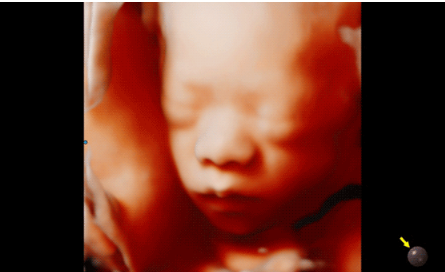

3D/4D成像方面,Hera i 10通過結(jié)合先進(jìn)的圖像渲染技術(shù),著重加強了邊緣和小結(jié)構(gòu)的可視化能力。